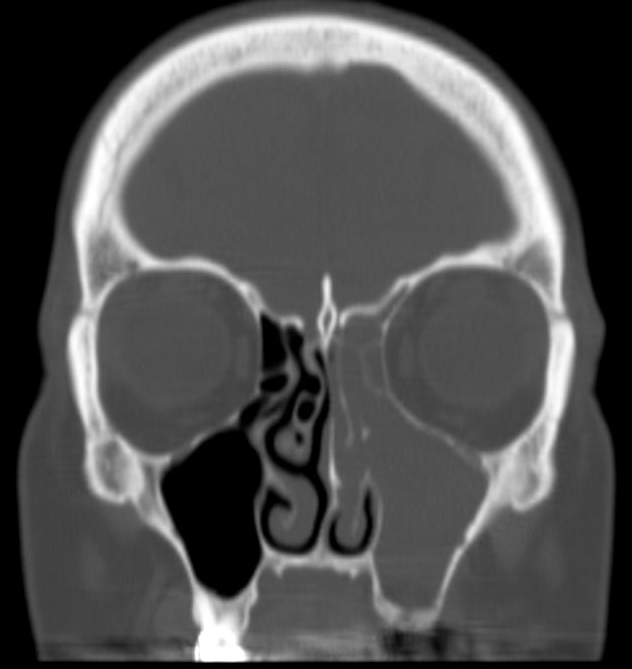

| A 69 year old female presents with 12 months of brown-yellow nasal drainage, mild right facial pressure, right nasal congestion and a foul taste and smell. She presented to her general dentist 3 months prior to her ENT consultation with a right gingival buccal lesion that resolved with clindamycin. A coronal CT image of the paranasal sinuses demonstrates maxillary and ethmoid sinusitis ipsilateral to right maxillary periapical tooth disease with buccal plate and maxillary sinus floor boney erosion. |

|

| A sagittal image through the right maxillary sinus shows periapical disease of teeth #2 and 3. This is another odontogenic sinusitis requiring dental treatment as the initial treatment for her sinus problem. |